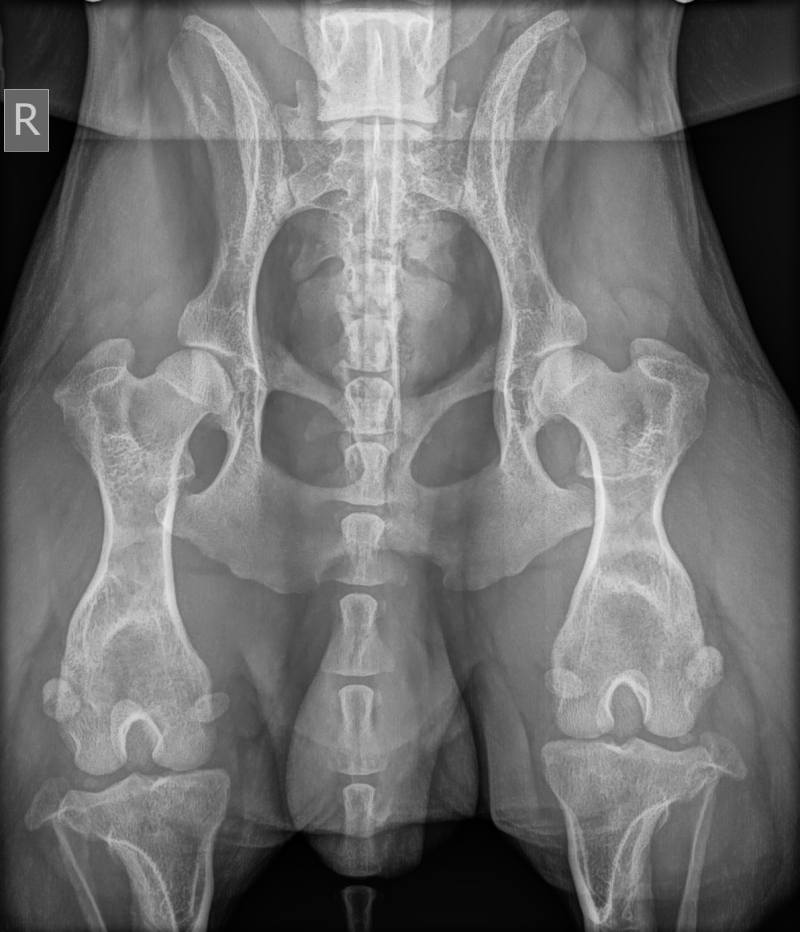

- heupdysplasie: FCI HD links B/rechts C (onder narcose aan de universiteit van Gent)

- heuplaxiteit: VMBDD links laag risico (LI 0,30 - 0,49), rechts hoger riscio (LI 0,50 - 0,69)